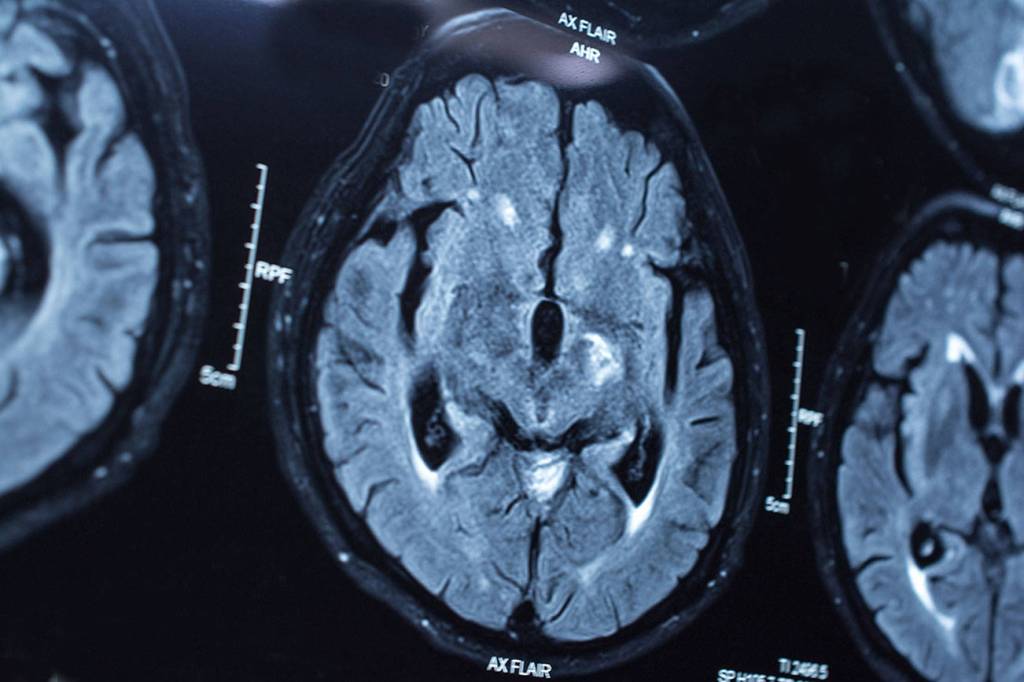

One of only three such examinations in the nation, the report looked at 47 common tests and treatments that are prone to overuse. Of those the study determined that 93 percent of overuse was attributable to 11 such procedures, including preoperative tests, lab studies before low-risk surgeries, too frequent screenings for cervical and prostate cancers, imaging for uncomplicated headaches, eye imaging for those without significant eye disease and others.

Fisk noted the overuse of CT scans for back pain, which often resolves itself within six weeks, and the prescription of antibiotics for ear infections and colds that aren’t effective treatments. But it’s often easier and quicker, Fisk said, to prescribe a pill than explain how unnecessary use of antibiotics is contributing to bacteria with greater resistant to antibiotics.

Along with the financial harm, Fisk said, there are risks to patients because of unnecessary exposure to radiation from X-ray, CT and MRI imaging; risks of infection; and emotional harm from tests that return false positive results, requiring in more tests and leading to anxiety and stress.